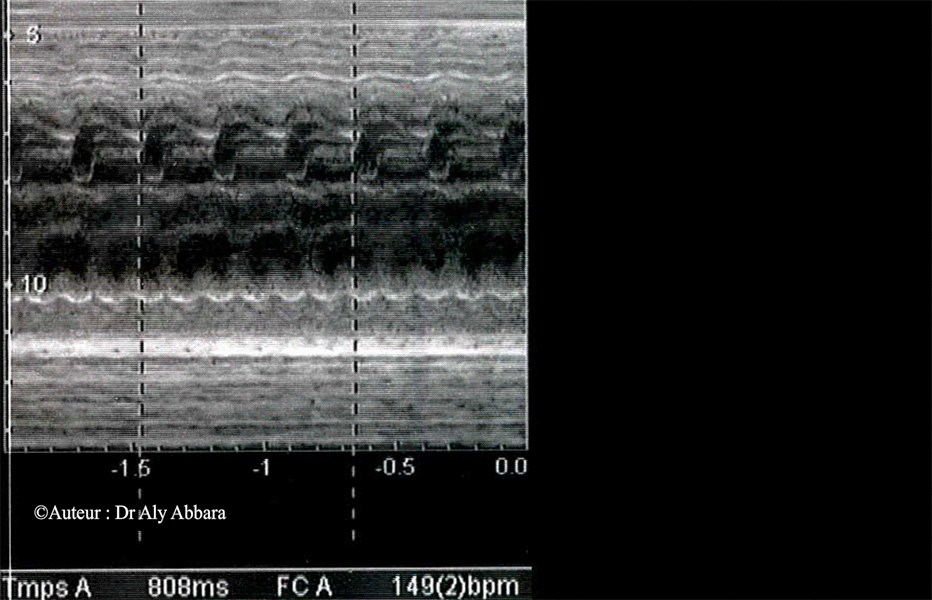

Flutter auriculaire - Foetus âgé de 37 SA

• Chez le fœtus, le flutter auriculaire se caractérise par une fréquence auriculaire supérieure à la fréquence ventriculaire.

• La fréquence auriculaire varie de 300 à 600 bpm ; elle est régulière.

• Le bloc auriculo-ventriculaire est variable :

• Quand il s'agit d'un bloc auriculaire de type "2:1", la fréquence ventriculaire est régulier et égale à la moitié de la fréquence auriculaire.

• Quand il s'agit d'un bloc auriculo-ventriculaire variable, il résulte une fréquence ventriculaire irrégulière de l'ordre de 150 à 250 bpm et un bloc auriculo-ventriculaire allant de 2:1 à 4:1.